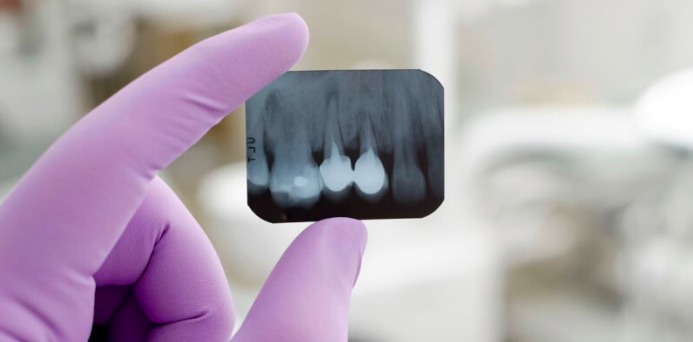

La correttezza di un trattamento endodontico dipende da due fattori:

- Pulizia efficiente del canale

- Sigillandolo per tutta la lunghezza

Con l’aiuto di strumenti moderni, si ottiene un ampliamento più accentuato del canale e una pulizia nettamente superiore e con i nuovi materiali di tenuta si ottiene un riempimento del canale perfettamente sigillato. La lunghezza del canale è ora misurata elettronicamente, quindi il medico sa esattamente fino a che punto ha raggiunto il riempimento del canale. Un isolamento più efficiente del dente assicura una prognosi a lungo termine molto migliore, poiché non esiste contaminazione intra operatoria con la saliva.